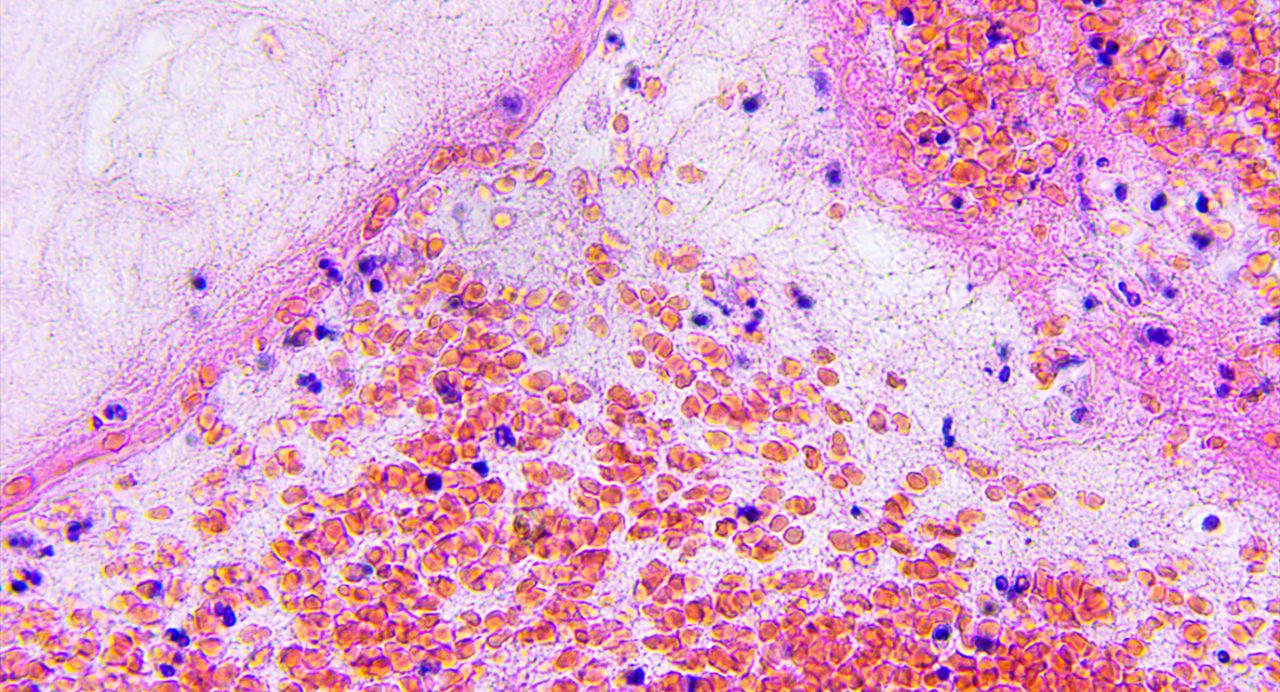

Natural killer (NK) cells engineered to express interleukin-21 (IL-21) demonstrated sustained antitumor activity against glioblastoma stem cell-like cells (GSCs) both in vitro and in vivo, according to new research from The University of Texas MD Anderson Cancer Center.

The preclinical findings, published today in Cancer Cell, represent the first evidence that engineering NK cells, a type of innate immune cell, to secrete IL-21 resulted in strong activity against glioblastoma, a cancer type in need of more effective treatment options.

In vivo, the IL-21 NK cells showed limited toxicity and excellent tumor control in murine models of patient-derived GSC, compared to high toxicity and ineffective tumor control with IL-15 NK cells, which became exhausted over time.